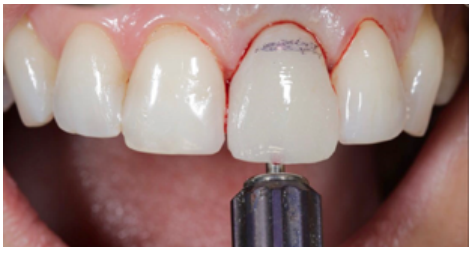

The benefits of immediate loading include a marked reduction in surgical interventions, less temporary dilation of the treatment and even better psychological and social wellbeing for the patient. In cases with a significant aesthetic requirement, immediate loading or provisionalisation, and post-extraction placement of the OII minimise alterations due to tooth loss and maintain the emergence profile, soft tissue contour and gingival papillae5-7.

Different protocols have also been established for the management of the anterosuperior aesthetic sector, in addition to performing the immediate implant and provisional crown, including placing material between the OII and the buccal cortical to minimise possible collapse and the management of peri-implant soft tissue8-11.